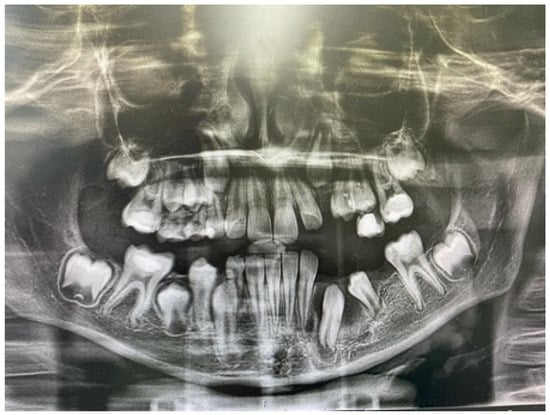

The orthopantomogram, brought by the patient, presented unycistic radiolucency with well-defined margins on the mandible’s right side as well as the left side of the maxilla. A multi-slice computed tomogram (MSCT) showed a cystic lesion in the maxilla extending from the second left permanent incisor to the first permanent molar. It included the unerupted follicles of the permanent canine, first, and second premolar, and was separated from the maxillary sinus by a thin bone. A second lesion was observed in the mandible, extending from the primary right canine to the first permanent molar. It also involved the crowns of the unerupted permanent teeth [Figure 5a,b].

Figure 5. Preoperative MSCT of a nine-year-old boy showing unicystic radiolucencies on the right side of the mandible (a) and left side of the maxilla (b).